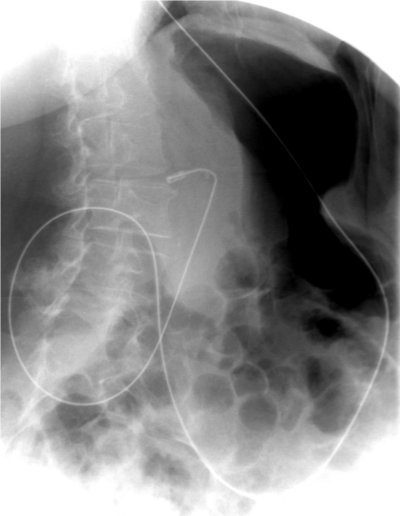

Coloscanner

Coloscanner et enteroscanner sont des techniques particulières du scanner pour explorer le tube digestif (intestin grêle et côlon). Ces explorations nécessitent une préparation avant l’examen et l’utilisation de produits de contraste (air, eau) pour distendre les organes et des produits de contraste par voie veineuse.